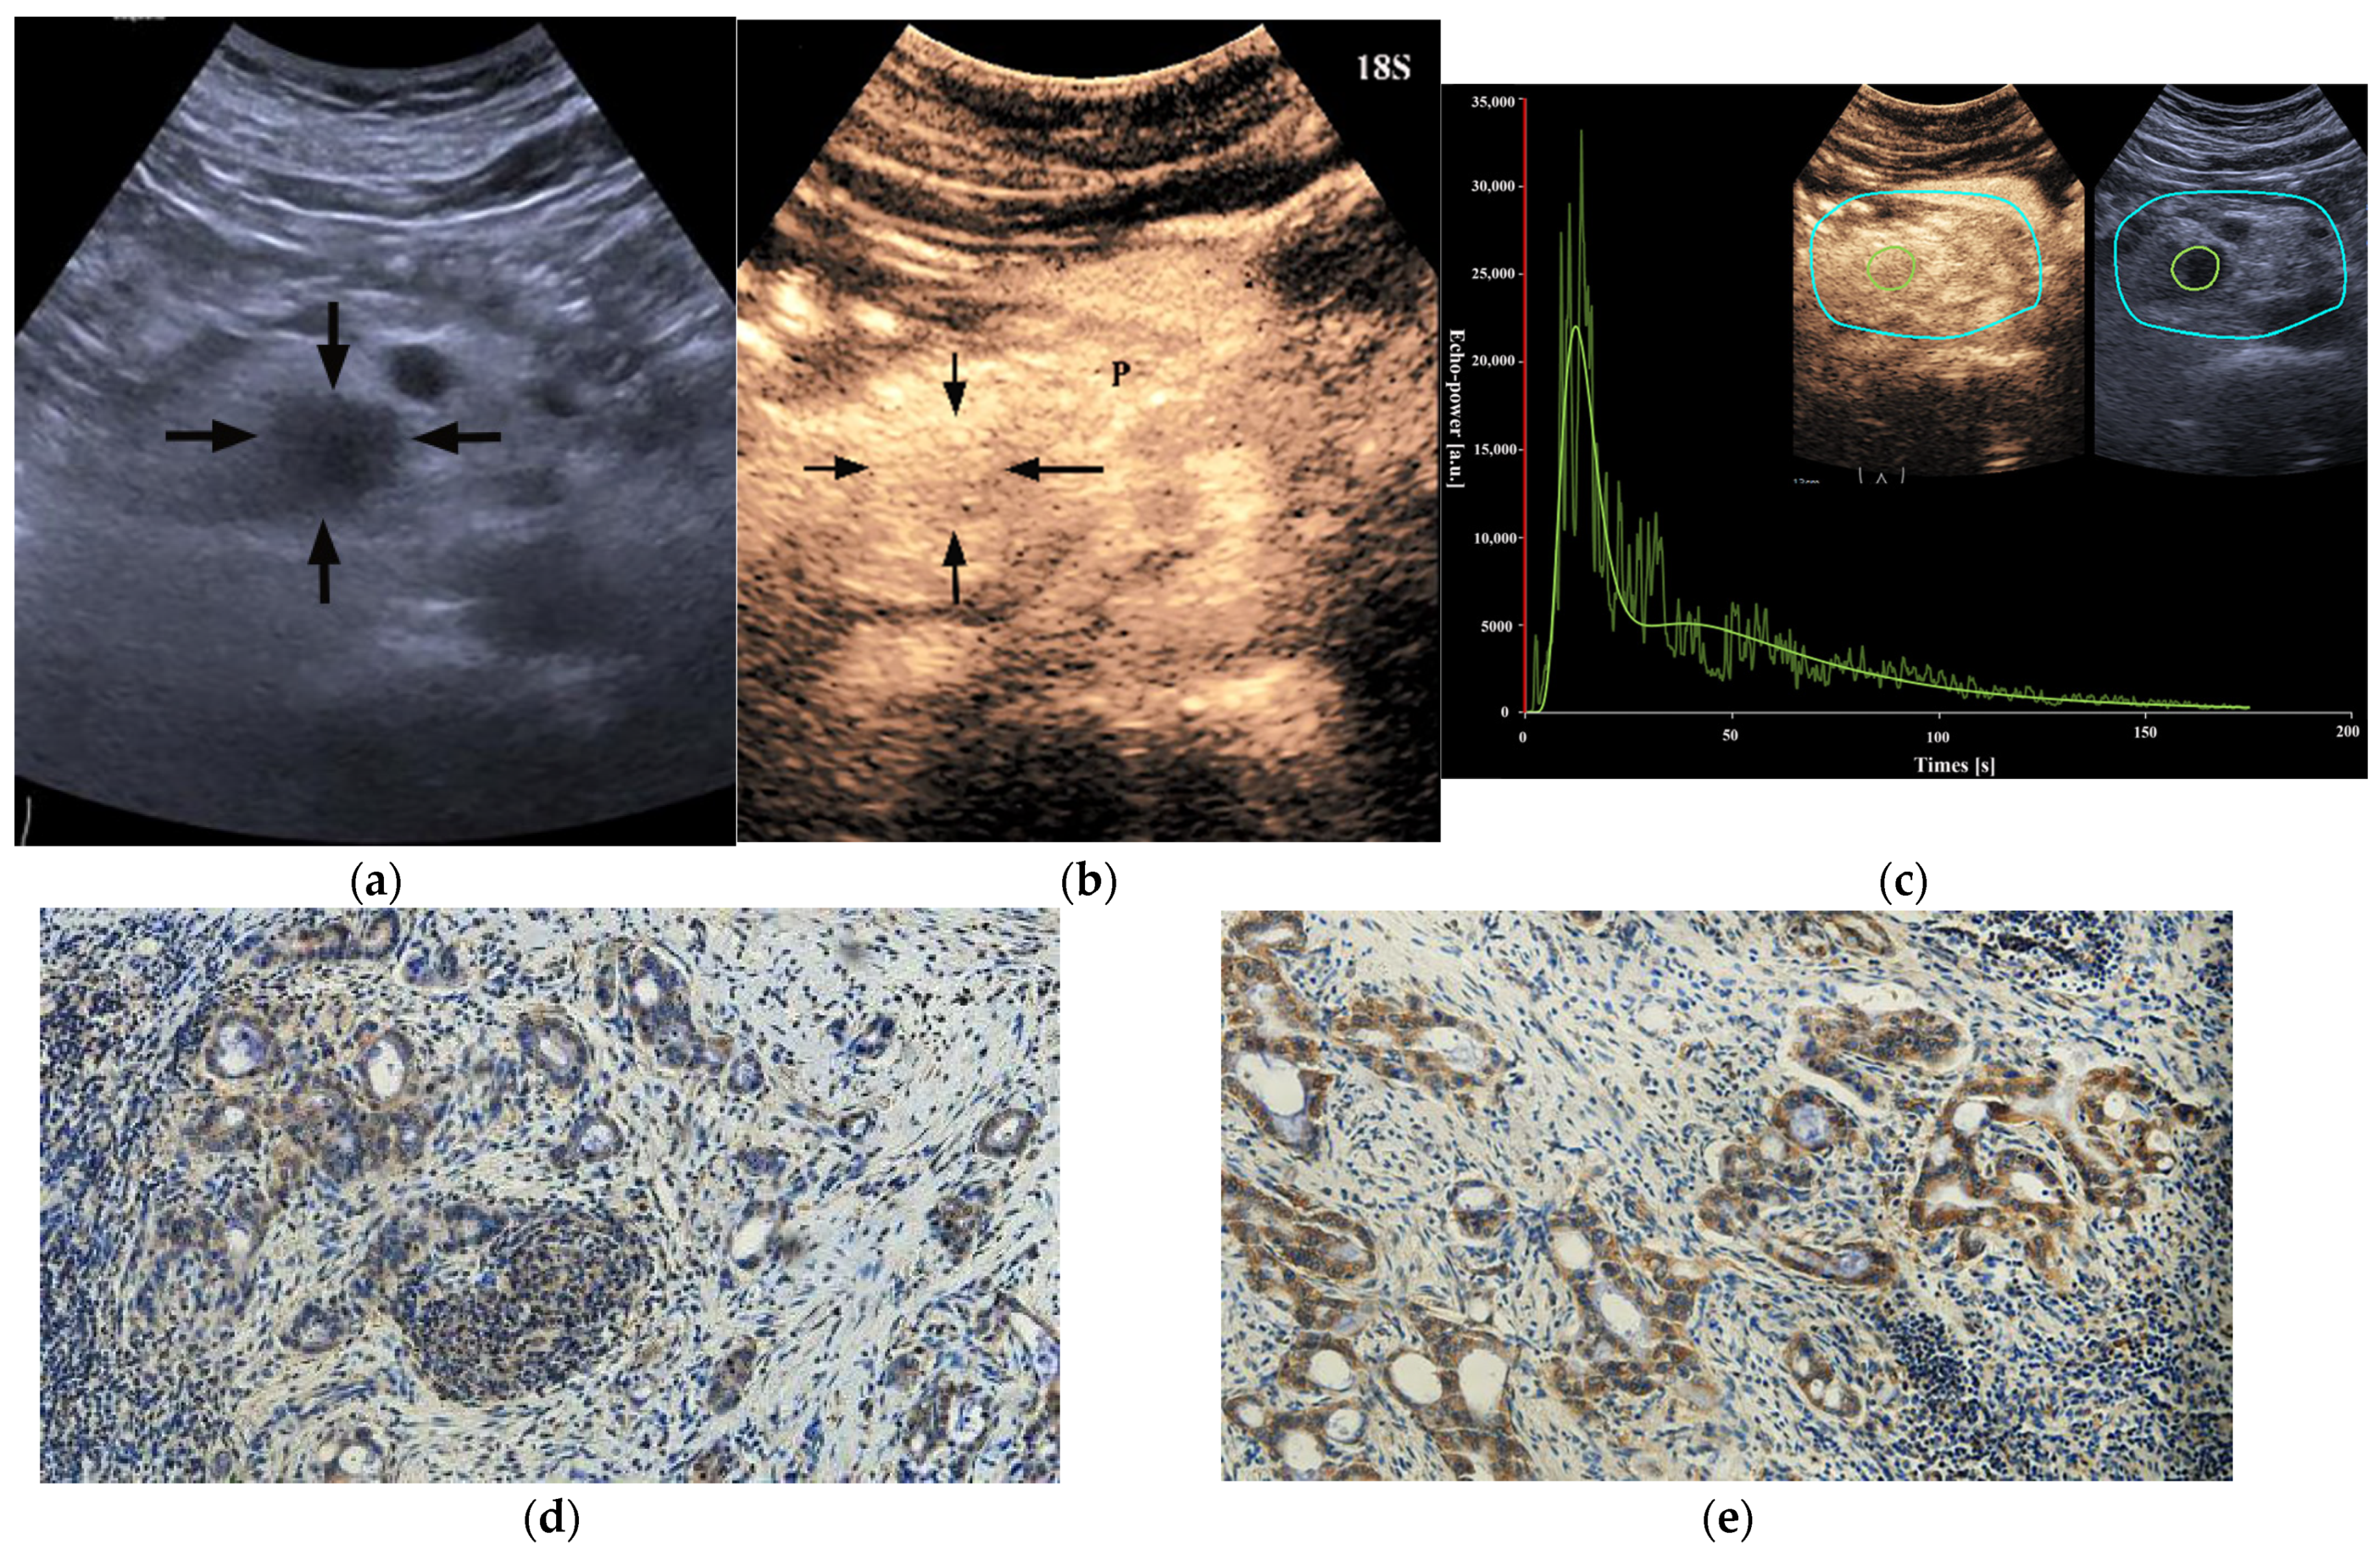

| Completeness of enhancement | ||||||

| Complete enhancement | 35 (68.6%) | 17 (33.3%) | 0.001 | 34 (66.7%) | 18 (35.3%) | 0.003 |

| Incomplete enhancement (enhancement > 50%) | 13 (25.5%) | 22 (43.1%) | 14 (27.5%) | 21 (41.2%) | ||

| Incomplete enhancement (enhancement ≤ 50%) | 3 (5.9%) | 12 (23.5%) | 3 (5.8%) | 12 (23.5%) | ||

| PED | ||||||

| Iso-enhancement | 9 (17.6%) | 19 (37.3%) | 0.027 | 8 (15.7%) | 20 (39.2%) | 0.008 |

| Hypo-enhancement | 42 (82.4%) | 32 (62.7%) | 43 (84.3%) | 31 (60.8%) | ||

| RT [s] | 8.0 (6.7–10.4) | 7.0 (6.2–8.7) | 0.154 | 8.0 (6.7–12.1) | 7.2 (6.0–9.7) | 0.067 |

| TTP [s] | 12.1 (9.7–16.0) | 11.3 (8.8–14.5) | 0.265 | 12.8 (9.8–15.9) | 11.2 (8.7–13.3) | 0.076 |

| PE [a.u.] | 10,693.4 (6566.8–20,600.4) | 16,173.8 (9381.0–27,237.6) | 0.024 | 10,125.9 (7037.8–18,662.1) | 15,939.4 (8939.2–27,388.2) | 0.018 |

| WIR [a.u.] | 1830.6 (868.4–4287.2) | 3607.1 (1973.7–5895.6) | 0.015 | 1898.3 (913.5–3844.3) | 3882.5 (1967.1–6205.7) | 0.002 |

| WiAUC [a.u.] | 57,775.0 (31,068.1–98,571.4) | 80,406.4 (45,124.3–123,632.3) | 0.169 | 57,933.7 (35,078.5–98,126.3) | 78,038.4 (43,797.8–133,500.0) | 0.334 |